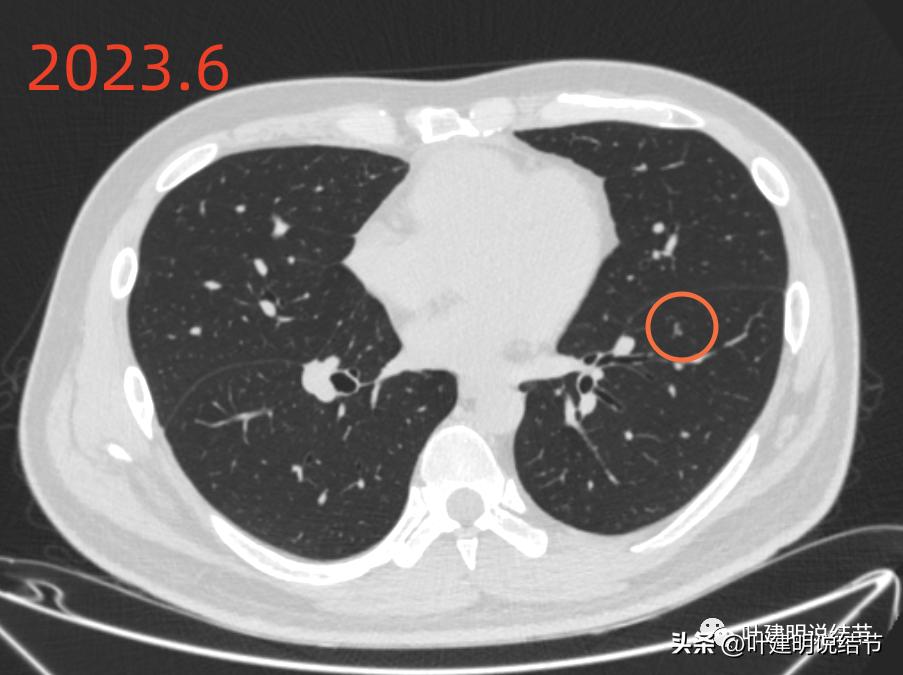

再来看2023年6月的影像情况:

左下病灶A仍在,感觉较前略有收缩,而且它旁边原来在2019年时有的磨玻璃结节已经完全吸收。考虑慢性炎可能性更大些。

左下病灶B持续存在,密度略有增高的样子,轮廓清楚,有微小血管征,仍要考虑肿瘤范畴的,以原位癌可能性稍大,大小无明显进展。

绿色圈起来的左上叶微小结节一直有,密度高,轮廓略糊,考虑是良性纤维增生结节;黄色圈起来的右侧的小片状磨玻璃影,非圆形或类圆形,且对比无进展,考虑是少许纤维增生。左下主病灶持续存在,轮廓较为清楚,但实性成分不明显,考虑不典型增生或原位癌可能性较大,目前风险不算高,个人以为仍可随访;左下次病灶密度显高,边缘略糊,不太像恶性。原来又炎症过,对比此前此处刚好是炎症较为明显的位置,所以比较符合慢性炎点,目前风险低,能随访。意见供参考!